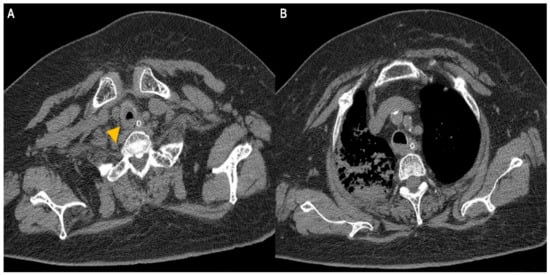

A 74-year-old woman was admitted to our hospital with dyspnea and chest pain. She had hypertension, type 2 diabetes mellitus, heart failure, persistent atrial fibrillation, and chronic obstructive pulmonary disease (COPD). The patient did not use an inhalant for COPD because of low adherence to inhalation therapy. Human immunodeficiency virus testing was negative. On the second day of admission, she complained of chest pain and showed a decrease in consciousness. Torsade de pointes and ventricular fibrillation were observed. She underwent intensive care unit (ICU) treatment for 10 days, including mechanical ventilation, direct-current cardioversion, and a temporary pacemaker. The patient received prednisolone from 5 mg to 10 mg per day with inhaled budesonide/salbutamol/ipratropium for two months from the day of ICU admission to treat the COPD exacerbation and control dyspnea. After being transferred to the general ward, the patient remained stable with tapering and discontinuation of steroid administration. The patient developed throat discomfort on the 68th day of hospitalization. Since then, her dyspnea gradually worsened without desaturation and CO2 retention. On the 76th day of hospitalization, the patient complained of sustained throat discomfort and dyspnea with stridor. Neck computed tomography revealed a narrowing of the proximal trachea with a diffuse wall thickening and intraluminal irregularity (Figure 1), and video laryngoscopy detected a tracheal mass-like lesion. On the same date, acute respiratory failure occurred (the oxygen saturation by pulse oximeter was 56%, and the respiratory rate was 32 breaths per min). CO2 retention was detected in the arterial blood gas analysis (pH: 7.037, PaCO2: 66.1 mmHg, PaO2: 205.3 mmHg) at 15 L/min via reservoir bag. The patient was transferred to the ICU for mechanical ventilation. There was no evidence of nosocomial pneumonia in the chest X-ray, and serum C-reactive protein was normal (<0.5 mg/dL). No severe obstructive respiratory pattern was observed on the flow graph of the ventilator monitoring, and the CO2 retention immediately improved after endotracheal intubation in low grade pressure support. On the second day after intubation, chest computed tomography showed an aggravation of the multifocal diffuse tracheal wall thickening with luminal narrowing (Figure 2A) and a new-onset peribronchial ill-defined consolidation in the right upper lobe (Figure 2B). The piperacillin-tazobactam was initially administered for treatment of pneumonia. Bronchoscopy revealed a proximal tracheal narrowing with multiple ulcerations of the tracheal mucosa surrounded by an erythematous margin (Figure 3A). Multiple biopsies were performed at the base and margin of the ulceration (Figure 3B). Microscopically, reactive squamous atypia was observed in the background of the ulcer and granulation tissue (Figure 4A). In the squamous epithelium, numerous keratinocytes with virus-infected changes, including ground glass nuclei and nuclear molding, and multinucleated giant cells were observed (Figure 4B). Immunohistochemistry showed positive results for the anti-HSV antibody. A few viral cytopathic cells were noted in the granulation tissue, which were positive for the anti-CMV antibody (Figure 4C). The CMV real-time polymerase chain reaction (PCR) in the bronchial alveolar lavage fluid was also positive (31,775 copies/mL). Therefore, intravenous ganciclovir (300 mg twice daily), which is effective against HSV and CMV, was administered for 44 days. Despite the cessation of the sedative drugs, the patient’s consciousness did not improve. Brain magnetic resonance imaging revealed a multifocal petechial hemorrhage in the bilateral temporo-parietal lobe and left insula and minimal subdural hygroma along the left cerebral convexity. These findings were consistent with hemorrhagic encephalitis. The cerebrospinal fluid examination was within normal limits (white blood cells, 1 cells/µL; protein, 43 mg/dL). The viral PCR results for enterovirus, CMV, HSV, and varicella-zoster virus were all negative. On the 19th day after intubation, a percutaneous dilatational tracheostomy was performed for the tracheal stricture. The patient was transferred to the general ward on the 29th day after ICU readmission. A follow-up bronchoscopy was performed about every two weeks. On the 44th day of ganciclovir therapy, the follow-up bronchoscopy showed an improvement in the ulceration with scars (Figure 5). Microscopically, no lesions were suspected from viral infection.

Figure 2. Chest computed tomography images. (A, arrowhead) Aggravated diffuse wall thickening with luminal narrowing at the proximal trachea. (B) Peribronchial consolidation and secretion stasis in the right upper lobe.